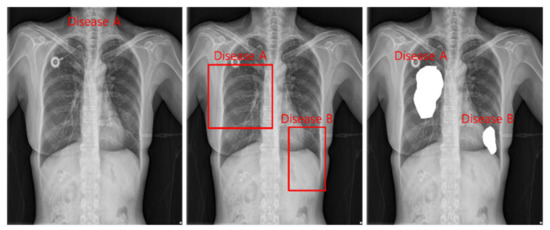

The tasks of deep learning currently utilized in health care are divided into classification, detection, and segmentation, as shown in Figure 2. Models used in all tasks utilize heavy and accurate SOTA models due to the nature of the medical field requiring refinement.

Classification is a task that divides negatives and positives by learning images and labels of diseases and is a method that focuses on learning for inferring disease names. For detection, a Bounding Box is marked around the location of a disease, and the disease name and Bounding Box coordinates are learned to infer the location information of the disease. Segmentation is a method of inferring the disease pixel by pixel by learning the location pixel of the disease.

Figure 2. Classification, detection, and segmentation task.